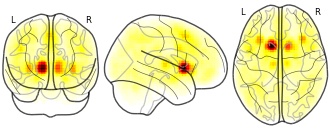

heather.wilson's temporary collection: Caudate_HD1

EmailClick to copy linkLink copied Cite(2016). heather.wilson's temporary collection: Caudate_HD1 [Dataset]. http://identifiers.org/neurovault.image:23677niftiAvailable download formatsUnique identifierhttps://identifiers.org/neurovault.image:23677Dataset updatedJul 4, 2016License

Cite(2016). heather.wilson's temporary collection: Caudate_HD1 [Dataset]. http://identifiers.org/neurovault.image:23677niftiAvailable download formatsUnique identifierhttps://identifiers.org/neurovault.image:23677Dataset updatedJul 4, 2016LicenseCC0 1.0 Universal Public Domain Dedicationhttps://creativecommons.org/publicdomain/zero/1.0/

License information was derived automaticallyDescriptionCollection description

Subject species

homo sapiens

Modality

PET other

Cognitive paradigm (task)

None / Other

Map type

R